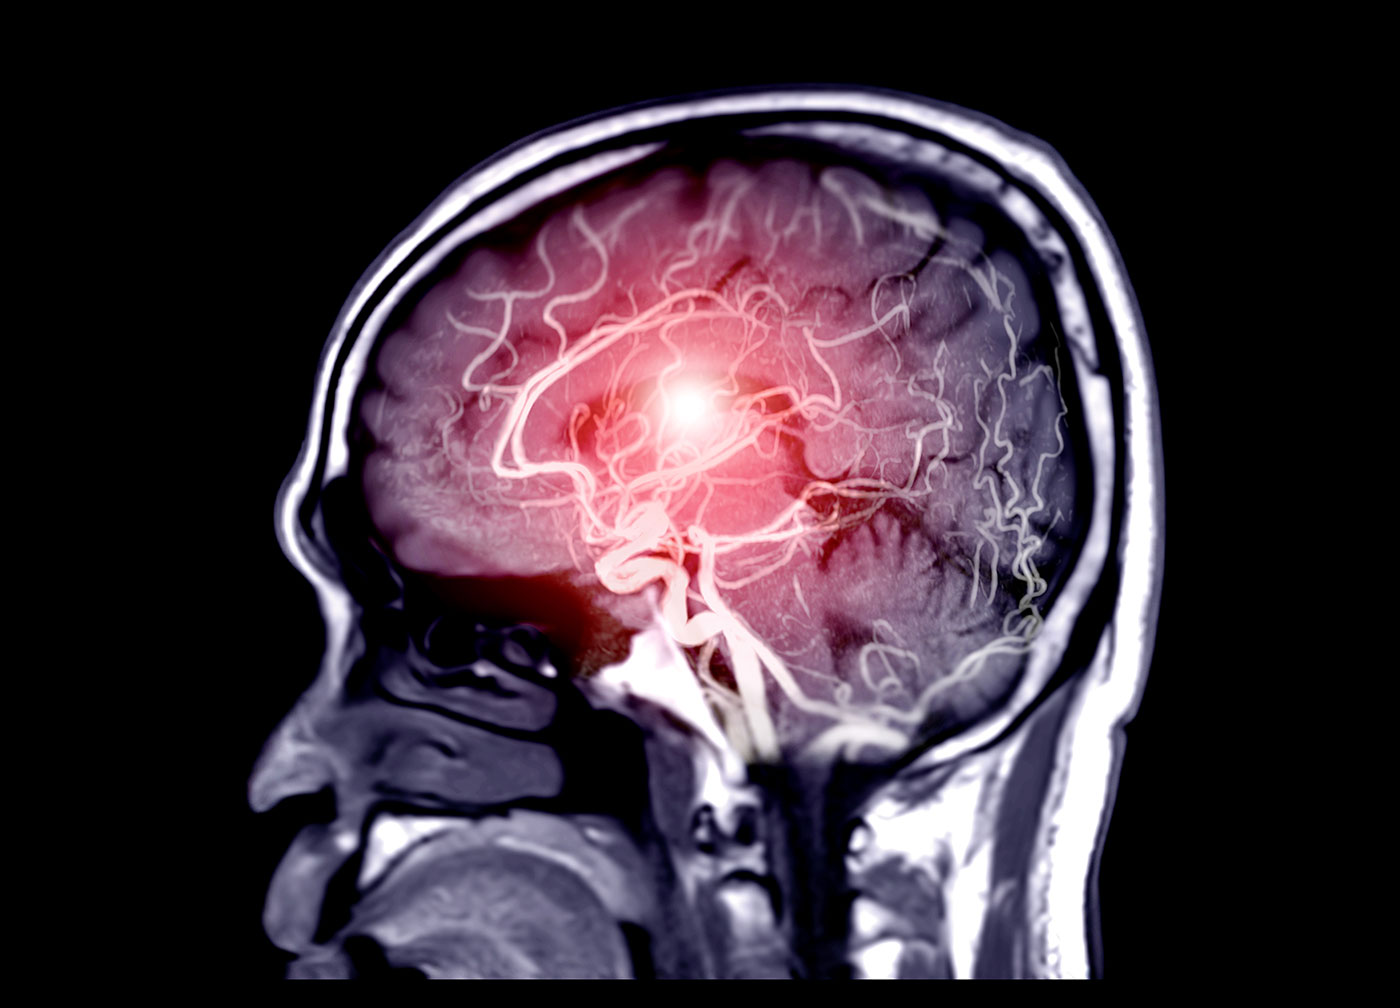

Una nova malla per tractar els aneurismes dins el cervell

Un implant trenat podria proporcionar una opció de tractament eficaç i mínimament invasiva per als aneurismes intracranials bifurcats, potencialment mortals.

Concretament, el Sistema Neurovascular Contour de Cerus Endovascular (Oxford, Regne Unit) està compost per un implant trenat de malla fina preformada amb propietats de memòria de forma i un sistema de col·locació de microcatèter. Aquest dispositiu combina un desviador i un interruptor de flux per apuntar al coll d'un aneurisma intracranial, lluny de la cúpula vulnerable.

Així mateix, el perfil de seguretat millorat permet el seu ús per tractar una varietat de morfologies i mides d'aneurismes, incloses les bifurcacions de coll ample no trencades.